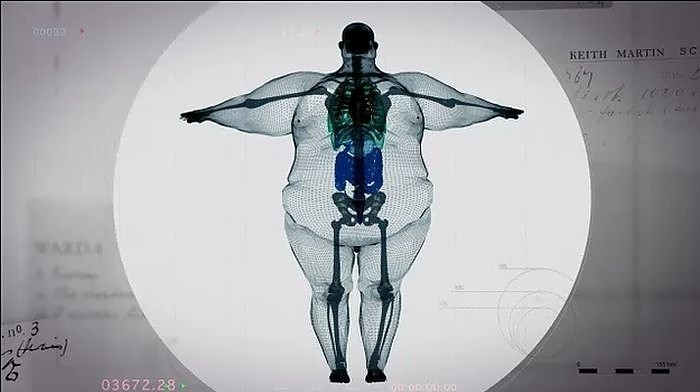

Martin, uzun yıllardır obezite hastasıDoktorlar, Martin eğer kilo vermezse 2 yıl ömrü kaldığını söylüyorlar.Martin’in Xray görüntüleri sosyal medyada büyük ilgi gördü. Çünkü Martin’in her insan gibi normal boyutta bir kemik yapısı vardıBu görüntüler zayıflamamak için kendine bahane bulan diğer kilolu insanları bilgilendirmek için dağıtılıyor.

Martin’in Xray görüntüleri sosyal medyada büyük ilgi gördü. Çünkü Martin’in her insan gibi normal boyutta bir kemik yapısı vardı